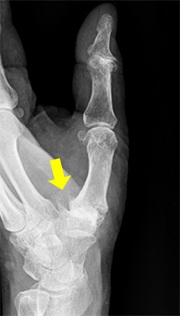

母指CM関節症の診断は問診や身体所見がとても大切です。当院では、問診や身体所見に加えてまず手関節X線撮影を行い関節変形の評価を行います。典型例ではCM関節の隙間が狭くなり、骨棘(こつきょく)の形成やCM関節の亜脱臼を認めます。

母指CM関節の変形、骨棘形成、亜脱臼を認める